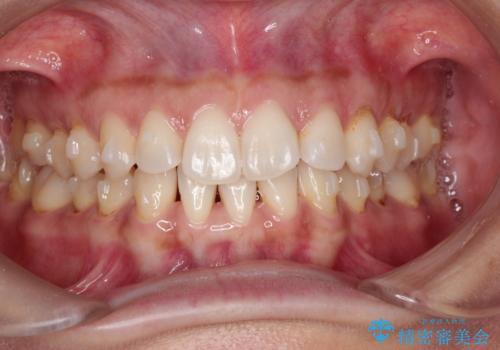

前歯のがたつきと隙間の矯正 インビザラインにて

- 上顎の前歯のがたつきと、下の前歯の隙間を主訴に来院されました。

下の前歯が先天的に欠損していました。

上顎の歯と歯の間をわずかに削りスペースを作り、ガタガタの改善し、下顎の前歯は隙間を閉じる計画としました。

非常に協力的な患者様でしたので、早期に治療が終了することができました。